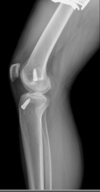

what is this finding called? association?

A

Segund fx

bony aculsion of anterolateral ligament

pathognominic for acl tear

associated with acl tear 75-100 percent of the time.